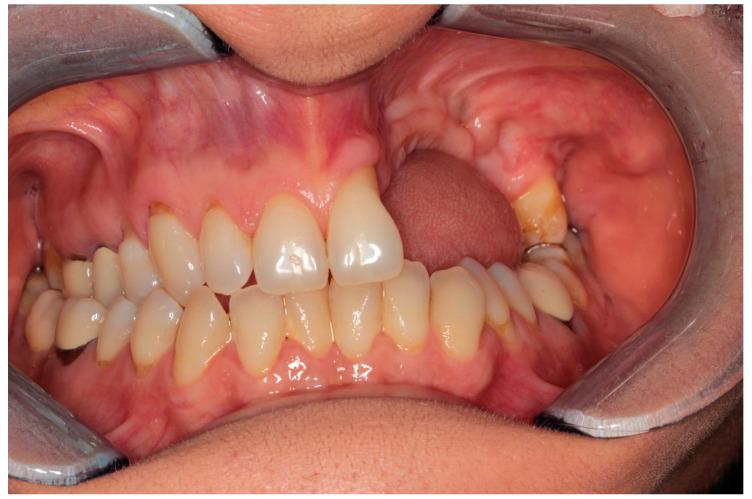

Medication-related osteonecrosis of the jaw (MRONJ) is a drug complication that can occur in patients taking antiresorptive or antiangiogenic drugs. Although it is a well-documented disease, there is no widely accepted treatment. However, several therapeutic approaches have been proposed. The surgical approach in many advanced cases appears inevitable; however, the results are not yet defined and predictable. This study aimed to propose a combined surgical approach with a piezoelectric device and laser (Er:YAG for bone ablation and Nd:YAG laser for photobiomodulation) in a young patient with breast cancer and bone metastasis under denosumab treatment, affected by spontaneous stage 3 MRONJ with maxillary sinus involvement. The patient under study reported no post-operative discomfort, with painkiller intake limited to the day after surgery. Total mucosal healing was observed without recurrences for more than 4 years after surgery. According to the results of our preliminary study, a combined surgical approach using a piezoelectric device and laser therapy is effective in managing patients affected by MRONJ, leveraging the clinical and biological advantages of these different techniques.

药物相关性颌骨坏死(MRONJ)是一种可发生于服用抗吸收或抗血管生成药物患者的药物并发症。尽管它是一种有充分文献记载的疾病,但尚无广泛接受的治疗方法。然而,已经提出了几种治疗方法。在许多晚期病例中,手术方法似乎不可避免;然而,其结果尚未明确且可预测。本研究旨在为一名接受地诺单抗治疗、患有乳腺癌和骨转移、受自发性3期MRONJ累及上颌窦影响的年轻患者,提出一种结合压电装置和激光(用于骨消融的铒:钇铝石榴石激光和用于光生物调节的钕:钇铝石榴石激光)的联合手术方法。研究中的患者术后无不适,止痛药服用仅限于术后当天。术后观察到黏膜完全愈合,4年多无复发。根据我们初步研究的结果,使用压电装置和激光治疗的联合手术方法在治疗受MRONJ影响的患者方面是有效的,利用了这些不同技术的临床和生物学优势。